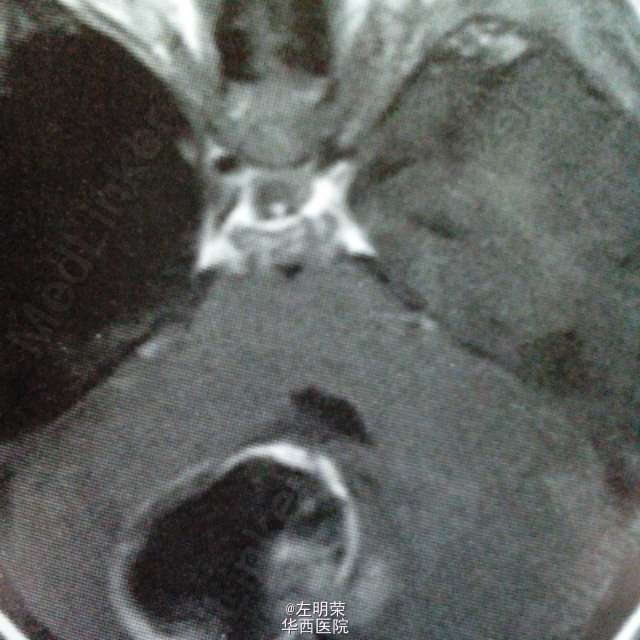

6岁小儿,主诉间断性头痛伴恶心,呕吐6天。影像特点:右侧小脑半球可见明显强化的囊实性占位,囊内可见出血后形成的液平,瘤旁轻微水肿。考虑星形细胞瘤,髓母细胞瘤,室管膜瘤可能。行手术切除治疗,见囊实性肿块,囊内坏死出血,肿瘤血供丰富,边界不清,近全切。病理结果:髓母细胞瘤